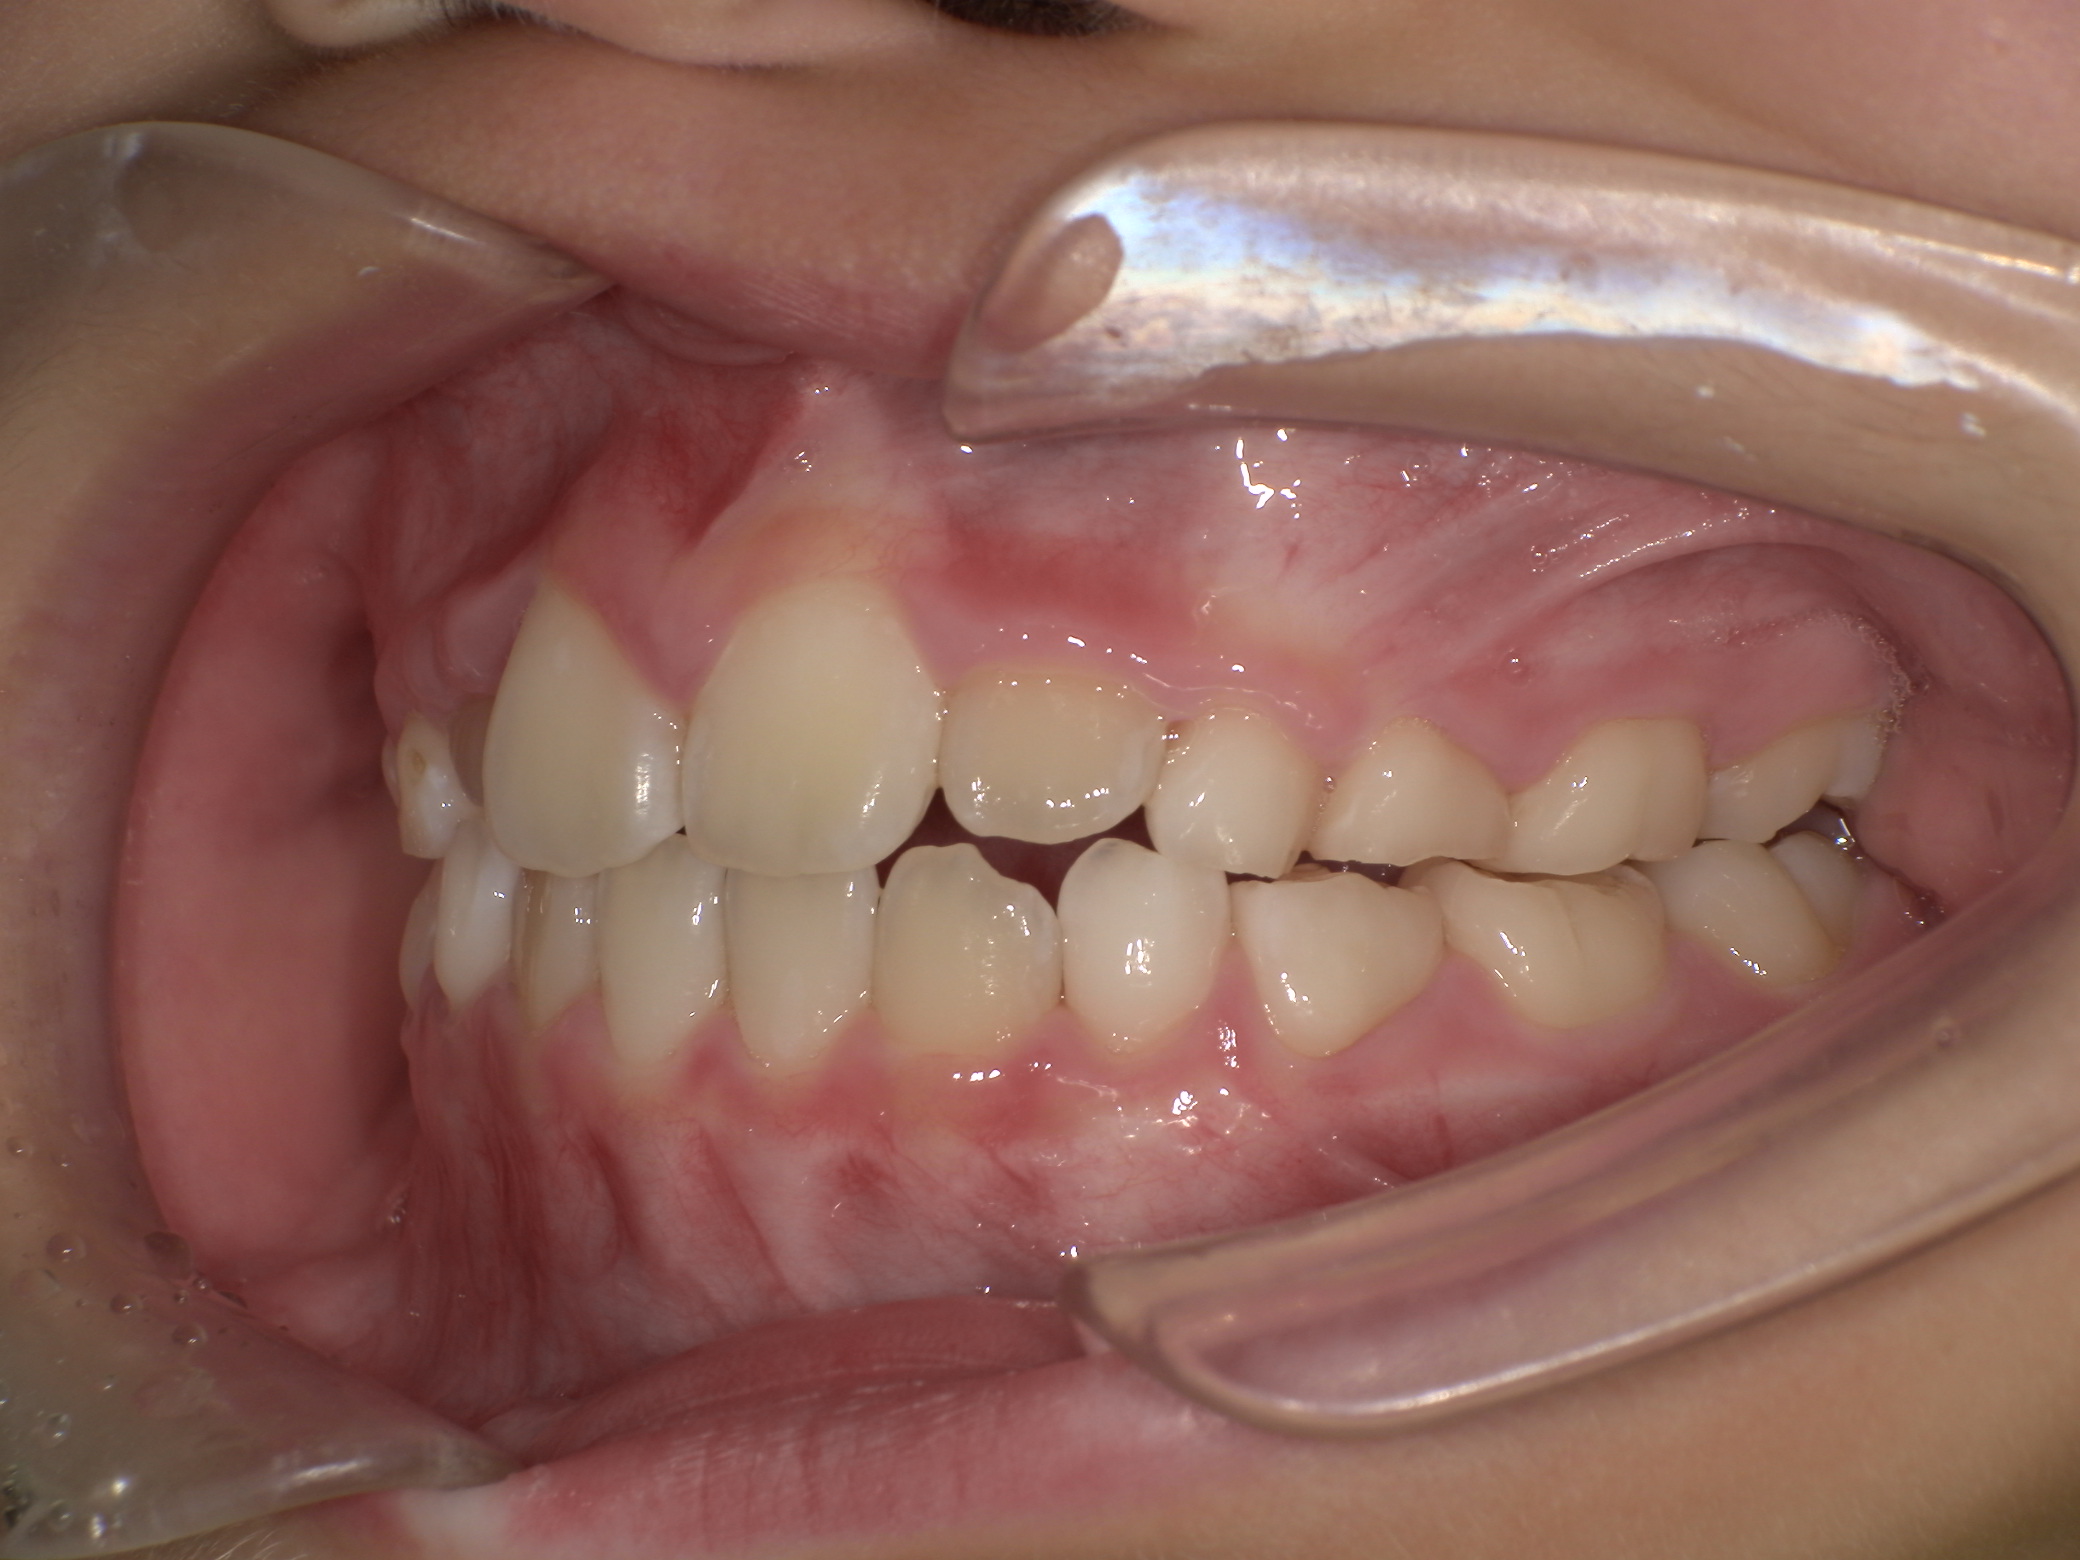

上写真:治療開始前(5歳2か月)

上の前歯が見えないくらいに下の前歯が出ていました。